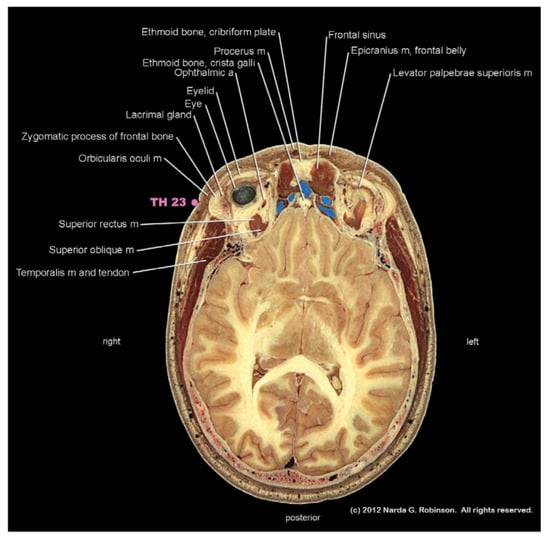

8.1. Head

8.1.1. Maxilla